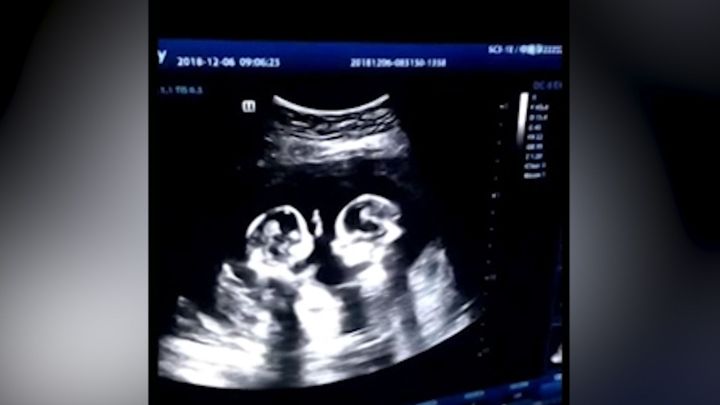

Dvojčetem je už každé 40. dítě, nejvíc v historii. Roli hraje věk matek i oplodnění

Svou roli v rekordním počtu dvojčat hraje asistovaná reprodukce a vyšší věk matek.